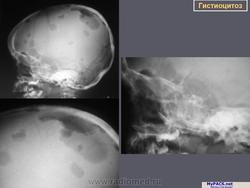

Изучение скелетограмм у 27 из 29 больных позволило выявить изменения, подтвердившие диагноз данного заболевания. Это указывает на высокую диагностическую ценность рентгенологического обследования при ГКЛ. Наиболее часто определялись поражения черепа в виде множественных (24) или единичных (3) дефектов в костях свода, где четко прослеживалась «штампованность» очагов. Дефекты не содержали секвестров, имели различную форму, величину, четкие наружные и неровные, фестончатые внутренние контуры. Периостальная реакция отсутствовала. При множественных участках деструкций картина напоминала «географический или ландкартообразный» череп, или «изъеденную молью ткань» (Рис.1).

Наиболее часто изменения выявлялись в височных костях (21), несколько реже в лобных (16) и теменных (14). Реже всего поражалась затылочная область (4), орбита (3), сосцевидные отростки (2). В 44% случаев отмечались сочетанные поражения черепа и других костей, в том числе: ребер (17), подвздошных костей (6), ключиц (4), крыши вертлужной впадины (3), лонных и седалищных костей (3), бедренных (4) и большеберцовых (4). При поражении костей таза, ребер, ключицы определялись разновеликие дефекты, между которыми нередко сохранялись костные перемычки, создающие картину сетчатой или ячеистой структуры. В типичных проекциях гиперостоз улавливался не всегда или был прерывистым. Опорными рентгенологическими симптомами являлись четкие фестончатые контуры очагов, однородность фона, отсутствие включений. Поражения в длинных трубчатых костях (Рис. 2) чаще локализовались в метафизарных отделах проксимальных концов. Деструктивные участки обычно располагались субпериостально, имели овальную или округлую форму, четкие полициклические контуры. Наибольший их размер был направлен вдоль оси кости. Кортикальные слой изнутри истончался или прерывался. Снаружи определялись периостальные наслоения в виде скорлупы, имеющие иногда слоистый характер.

Рис. 1. Боковая краниограмма, больной Б. С., 3 года. Множественные литические очаги деструкции в костях черепа.